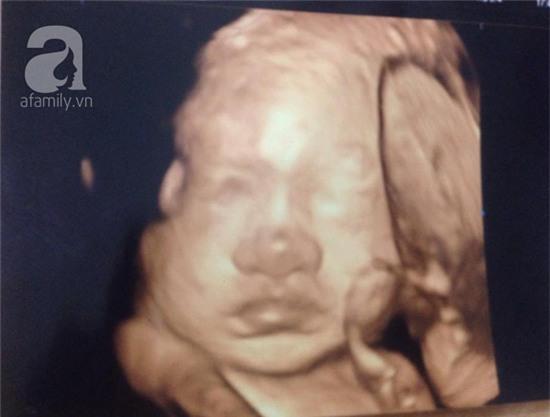

Về thông tin người nhà cho hay, sản phụ trước đó đã có kết quả siêu âm thai nhi hơn 4kg, giám đốc bệnh viện khẳng định điều này hoàn toàn sai sự thật. Bác sỹ Quyết cũng cho rằng, chỉ có thể người này đánh tráo kết quả bằng cách nhờ người có bầu thật vào khám rồi khai tên của mình.